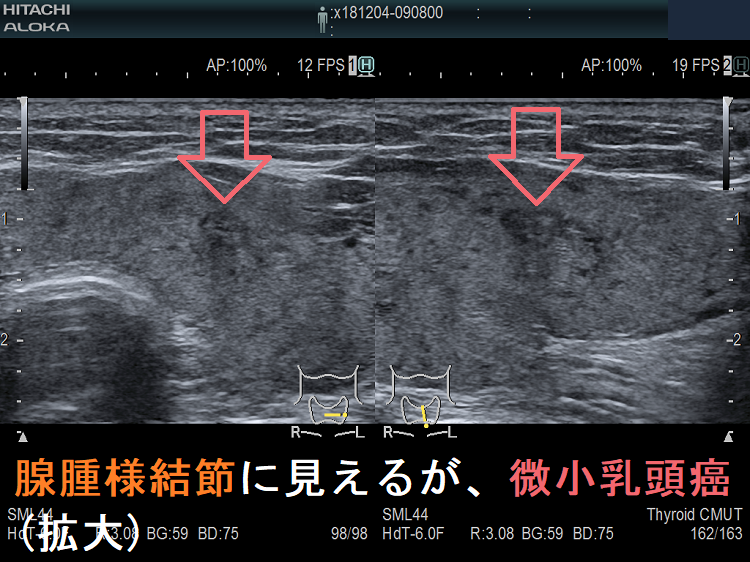

しかし、長年、甲状腺超音波(エコー)検査を行ってきた筆者の経験では、そこまで多くないと感じていました。ところがギッチョン、思わぬ落とし穴が・・・。甲状腺超音波(エコー)上、どう見ても腺腫様結節で甲状腺微小乳頭癌とは思えないものがあります。エラストグラフィーでも軟らかく、細胞診をする必要性も感じません。それが、まさかの甲状腺微小乳頭癌だったのです。

ケース①